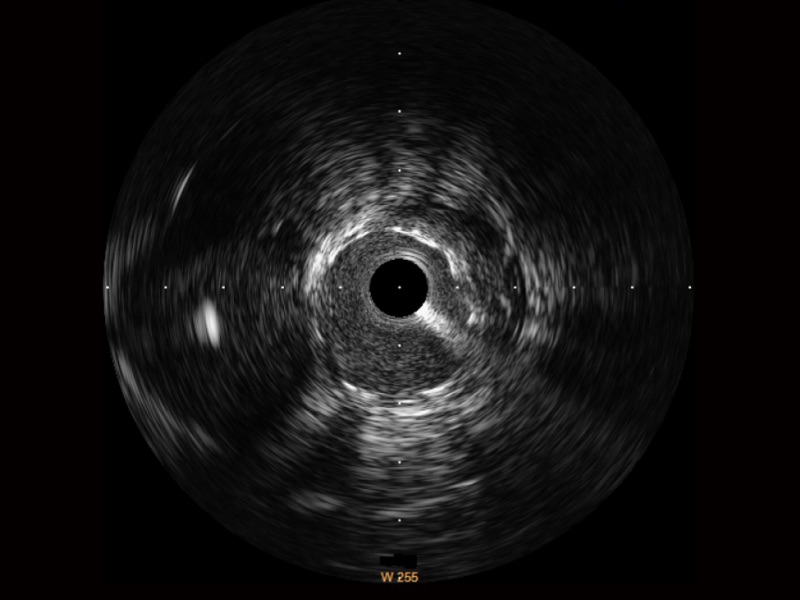

• milan米兰宽频IVUS图像

• 传统IVUS图像

对比传统IVUS导管成像,milan米兰宽频IVUS图像的近场支架梁显影更细腻,远场中膜外血管仍清晰可辨,兼顾远中近,兼顾分辨力与穿透深度